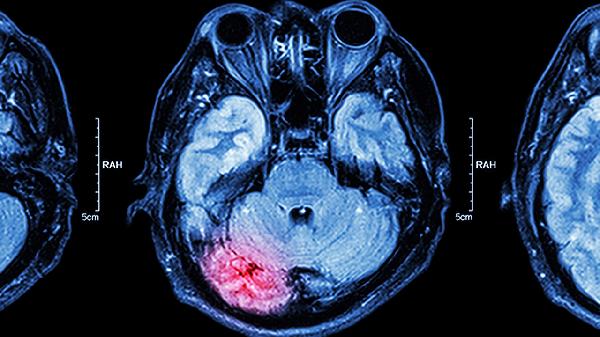

出现上述症状建议尽早就诊神经内科,通过头颅CT或MRI明确病变性质。康复期需进行针对性功能训练,语言障碍者可用图片交流板辅助沟通,运动障碍患者应预防跌倒和关节挛缩。饮食注意补充B族维生素和欧米伽3脂肪酸,避免高盐高脂饮食加重脑血管负担。